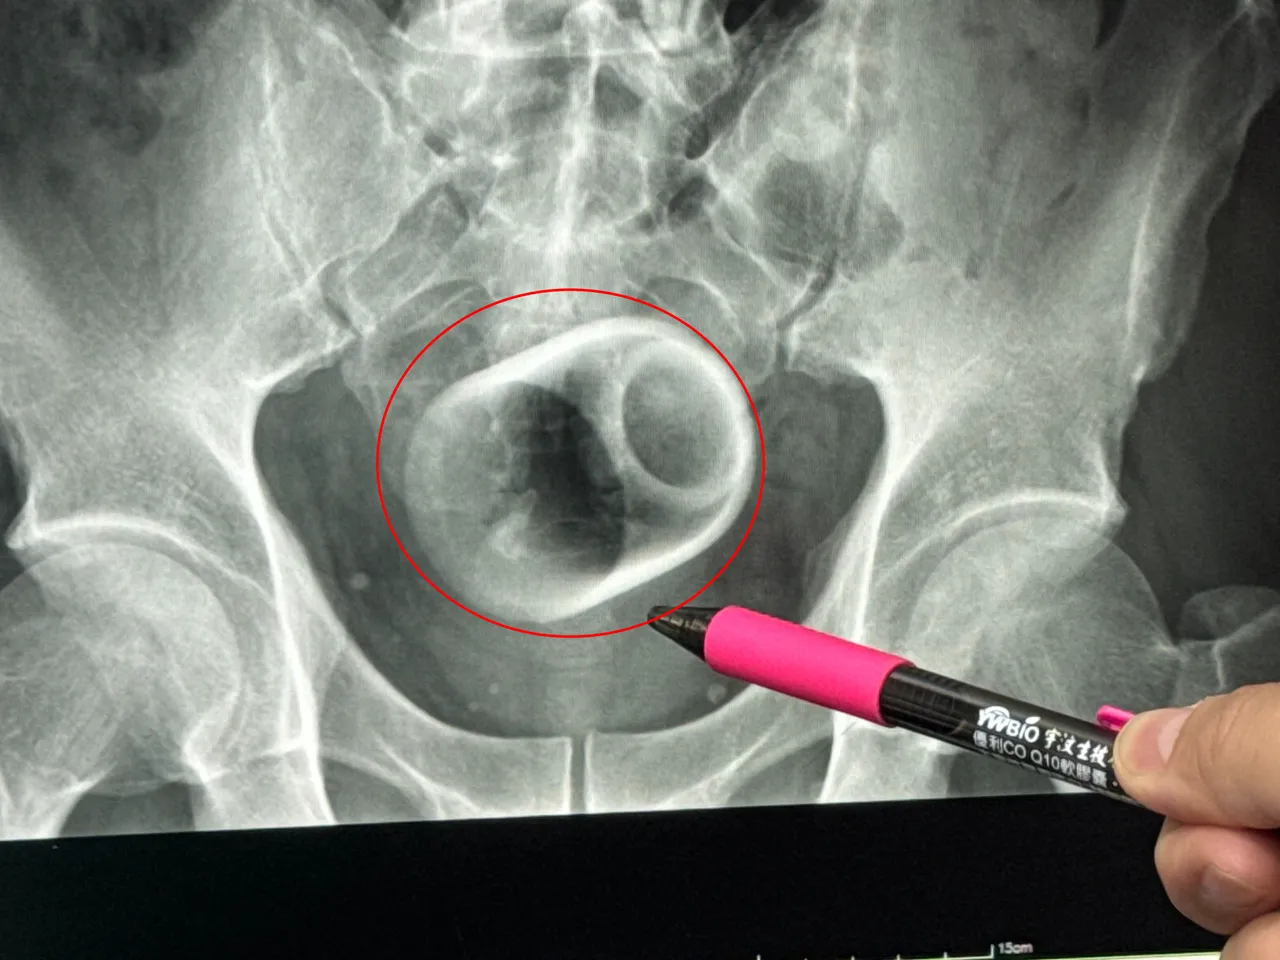

一名男子把陶瓷杯塞进肛门,X光片显示杯子位于骨盆腔内。李综合提供

驻诊在李综合医院的台中荣总外科医师吴坤达表示,该名患者到院时,自诉3天无法大便非常困扰,害羞不敢提及自己肛门塞了一个杯子,经过X光摄影,看到骨盆腔内有一个杯子,杯口朝下,因此,马上安排进手术室,要把杯子拿出来。